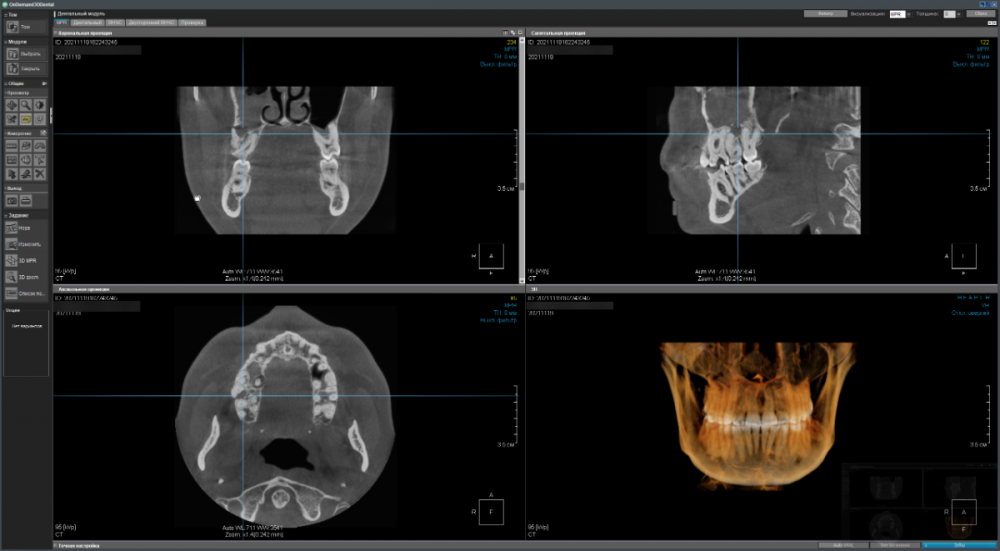

Имеется два сильно запущенных зуба на верхней челюсти справа - хотелось бы понять имеет ли смысл пытаться вылечить их терапевтически (чтобы потом поставить коронки) или уже поздно и надо/лучше удалить (и установить импланты)?

CDViewer_MseUIjLWPK.png